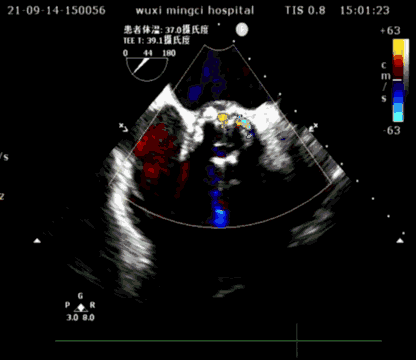

超声短轴

超声长轴

瓣膜植入后,压差从术前70mmHg降至10mmHg以下,瓣膜形态良好,手术圆满成功。